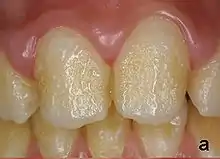

Pitting enamel hypoplasia

Enamel hypoplasia can take a variety of forms, but all types are associated with a reduction of enamel formation due to disruption in ameloblast production.[1] One of the most common types, Pitting Enamel Hypoplasia (PEH), ranges from small circular pinpricks to larger irregular depressions.[2] Pits also vary in how they are occur on a tooth surface, some forming rows and others more randomly scattered.[3] PEH can be associated with other types of hypoplasia, but it is often the only defect observed.[4] Causes of PEH can range from genetic conditions to environmental factors, and the frequency of occurrence varies substantially between populations and species, likely due to environmental, genetic and health differences. The most striking example of this is in Paranthropus robustus, with half of all primary molars, and a quarter of permanent molars, displaying PEH defects, thought to be caused by a specific genetic condition, amelogenesis imperfecta.[1]

Each pit is linked to the ceasing of ameloblasts at a particular point in enamel formation. Sometimes, only a couple of ameloblasts stop forming enamel, leading to small PEH defects, with large pits forming when hundreds of these enamel-forming cells stop production.[6] This does not occur in other forms of enamel hypoplasia, such as linear and plane-form, in which all ameloblast activity is affected.[4] Typically with PEH described in archaeological reports, researchers can not specify a cause, with a non-specific stress often concluded. However, in modern clinical studies it is often possible to suggest a cause and these can include the following conditions:[1]